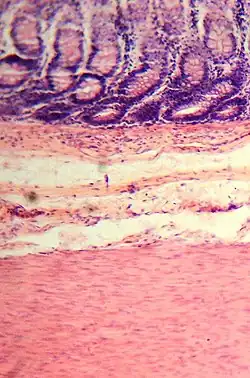

Histological section.

The wall of the large intestine is lined with simple columnar epithelium with invaginations. The invaginations are called the intestinal glands or colonic crypts.

The large intestine absorbs water and any remaining absorbable nutrients from the food before sending the indigestible matter to the rectum. The colon absorbs vitamins that are created by the colonic bacteria, such as thiamine, riboflavin, and vitamin K (especially important as the daily ingestion of vitamin K is not normally enough to maintain adequate blood coagulation).[36][37] It also compacts feces, and stores fecal matter in the rectum until it can be discharged via the anus in defecation.